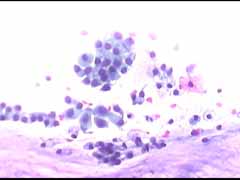

Στο ιατρείο μας διενεργούμε από ανέκαθεν την λήψη, χρωση κι άμεση μικροσκοπική εξεταση ενός επιχρίσματος κατά Papanicolaou. Για τον σκοπό αυτό εφαρμοζουμε την κλασική χρώση κατά Παπανικολάου και κατα τελευται 4 χρόνια επιπλέον και την χρώση Cytocolor της εταιρειας Merck , που διαρκεί μονον 4 λεπτά και δινει εντυπωσιακές εικόνες, ειδικά στην απεικόνιση των αδενικών κυττάρων. Τα παρακάτω περιστατικά είναι μία επίδειξη φυσιολογικών κυτταρολογικών εικόνων γυναικών στην εμμηνόπαυση και κλιμακτήριο..

Papanicolaou. Τυπική εικόνα ατροφιας επιθηλίου με παρουσία κυτταρων κυρίως της παραβασικής και λιγότερο της διαμέσου στοιβάδος, με την αναμενόμενη πολυμορφία της ατροφίας του επιθηλίου και τις αναμενόμενες εκφυλιστικές αλλοιώσεις.. Αρκετά κύτταρα ενδοτραχήλου κατα μόνας και καθ΄ ομάδας.. Λιγα πολυμορφοπύρηνα. Αρνητικό για κακοήθεια..Φυσιολογικό για την ηλικία.